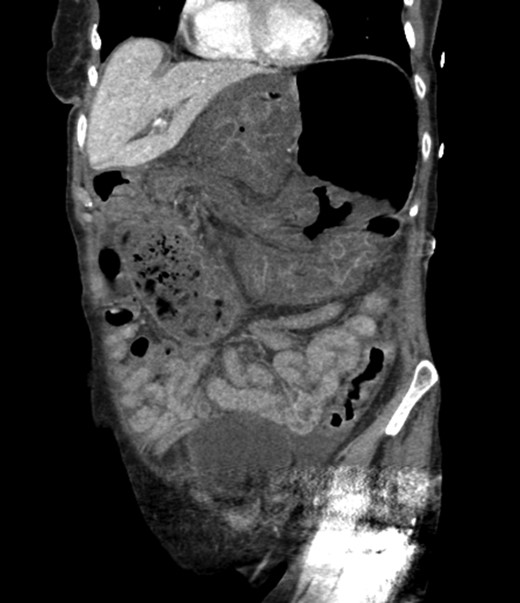

An 81-year-old female with a medical history of CAD with stents, hyperlipidemia, hypothyroidism, GERD, recent UTI, pancreatic cyst, constipation, anemia and leukopenia presented to the ED with a 1 day history of mild, diffuse and cramping abdominal pain. The patient was unable to give an accurate history, but the son at bedside supplemented this reporting that for several years the patient had been experiencing ill-defined abdominal discomfort. Physical exam showed a soft abdomen with mild tenderness and no evidence of peritonitis. A CT scan of the abdomen and pelvis with IV and PO contrast (Fig. 1) showed edematous changes to the mesentery of the small and large bowel with swirling of vessels indicative of internal hernia. The stomach was also noted to be distended with both air and fluid as a consequence of posterior compression by the hernia contents (Fig. 2). A surgical consult was obtained, a nasogastric tube and Foley catheter were placed, antibiotics were started, and the patient was taken for an exploratory laparotomy. Upon entering the abdomen through a vertical midline incision, 1.5 l of ascites was drained revealing a diffusely edematous mesentery. A large portion of the small bowel was seen to be herniated through the Foramen of Winslow (Fig. 3). A Kocher maneuver and division of the gastrocolic ligament were then performed to allow release of the herniated small bowel. It was at this time that, in addition to small bowel, a large portion of the ascending and transverse colon was noted to be herniated through the foramen of Winslow. The small bowel was also seen to be torsed about its own mesentery. Normal anatomy was restored and the bowel noted to be healthy and viable with peristalsis (Fig. 4). Due to the large size of the foramen after reduction and enlargement, it was deemed best to leave it open to prevent any further incarceration or strangulation. The abdomen was closed and the patient tolerated the procedure well. At a follow-up visit 2 months later, the patient had well-healed incisions, was doing well, tolerating a diet, and gaining weight appropriately.

Loops of bowel between IVC, liver, and lesser curvature of the stomach. Arrow small bowel. Arrow head stomach.

Diagnosing an internal hernia is frequently accomplished using physical exam and CT imaging. Abdominal X-ray does have some nonspecific findings suggestive of internal hernia but is usually inadequate for diagnosis. Diagnosis of a foramen of Winslow hernia, however, is only accomplished in 10% of patients preoperatively [3]. As previously mentioned this diagnosis is rare and often presents with vague obstructive type symptoms. This likely contributes to the low occurrence of accurate preoperative diagnosis. However, several radiographic findings were seen in this patient that suggested a foramen of Winslow hernia preoperatively. First, there is visible swirling of the mesentery on the CT scan that is indicative of internal hernia (Fig. 1). Second, there are loops of small bowel that can be visualized between the IVC and the edge of the liver in a supra renal position along the lesser curvature of the stomach (Figs 1 and 2). When compared to a CT of the abdomen and pelvis obtained 4 years prior to presentation, there is actually evidence that this patient had a non-obstructing foramen of Winslow hernia at that time as demonstrated by bowel being visualized in the lesser sack (Fig. 5). These findings, especially small bowel along the lesser curvature of the stomach, are inconsistent with normal anatomy and strongly indicative a foramen of Winslow hernia.

CT abdomen and pelvis coronal view of foramen of Winslow hernia.